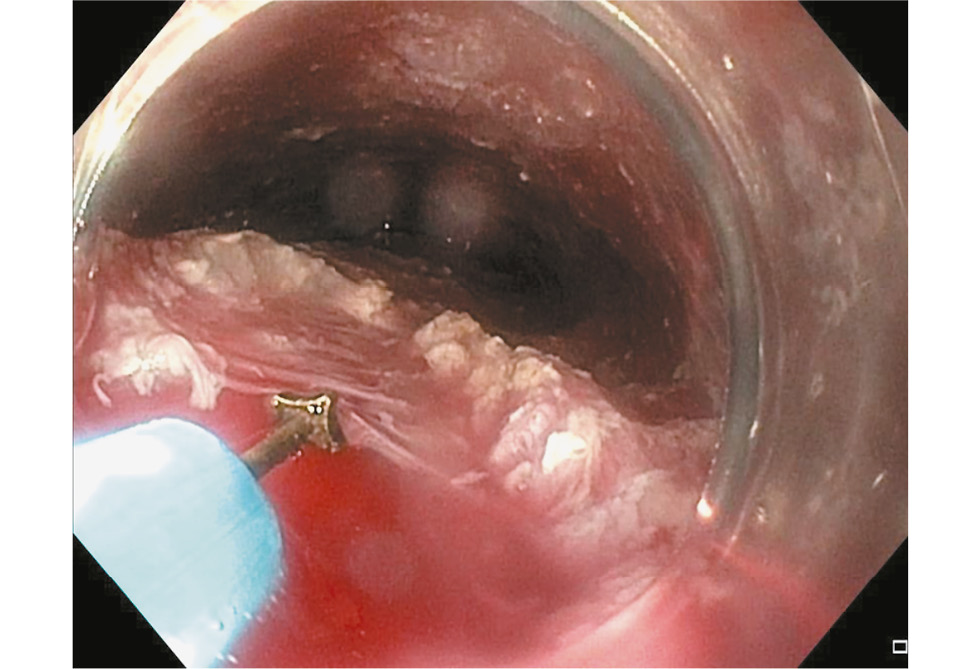

Всем пациентам диагноз был поставлен на основании клинических данных и дополнительных методов обследования. Клинические данные включали жалобы и срок заболевания. Основными методами обследования, которые подтвердили диагноз, являлись эзофагогастродуоденоскопия (ЭГДС) (рис. 1) и эзофагография (рис. 2).

Рис. 1. Эзофагогастродуоденоскопия: эзофагит и выраженное сужение пищевода.

Fig. 1. Esophagogastroduodenoscopy: esophagitis and narrowing of esophagus.

- контрастной эзофагографии, которая выявила характерные рентгенологические признаки АП: значительное расширение просвета пищевода, наличие в пищеводе остаточного содержимого, отсутствие отчётливого газового пузыря в желудке и признак «птичьего клюва»;

- ЭГДС, на котором выявлено стойкое сужение кардиального жома, ослабление перистальтики пищевода, отсутствие расслабления НПС и сужение пищевода на уровне НПС;